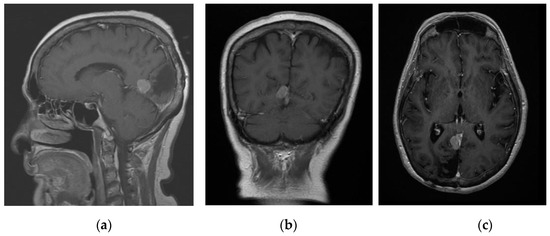

The next patient was a 67-year-old female presenting with right-sided weakness. On examination, she was noted to have grade 3/5 on the right upper and lower limb. MRI brain with contrast showed a 3.6 × 2.7 × 1.4 cm left frontal convexity tumour with features consistent of that being a meningioma (Figure 4). Patient was counselled for craniotomy and resection of tumour under general anaesthesia.

Figure 4. Contrasted T1 MRI showing homogenously enhancing frontal convexity meningioma.